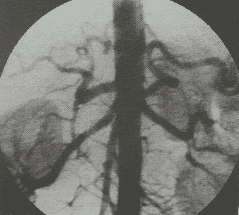

Chụp số hóa xóa nền động mạch não

Chụp động mạch não bằng máy số hóa xóa nền cho phép chẩn đoán, phát hiện các bệnh lý mạch não hoặc nghi ngờ những chấn thương do tai nạn gây tổn thương động mạch não.